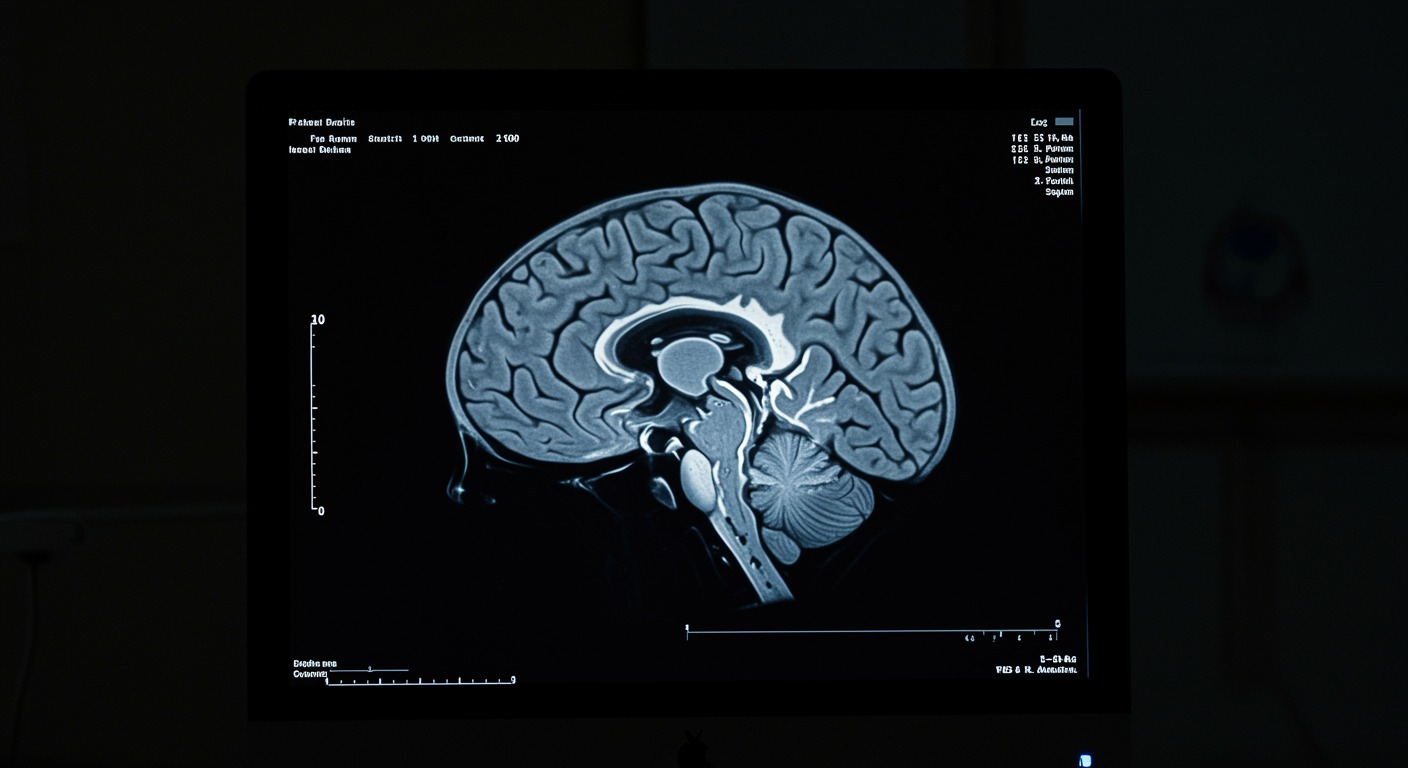

Why Cancer Causes Depression: The Tryptophan-Inflammation Connection